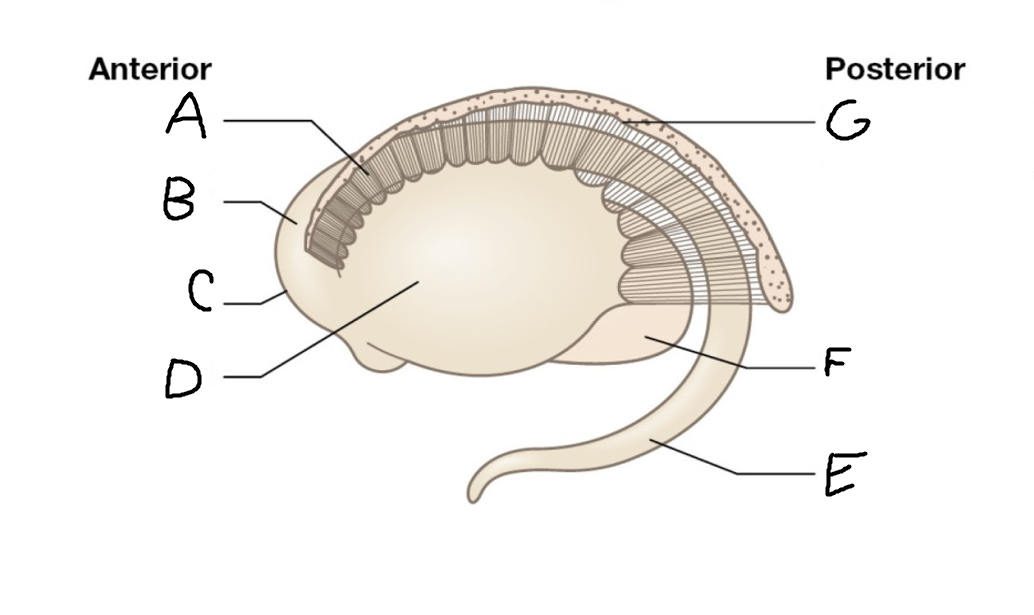

A

caudate nucleus head

C

caudate tail

D

globus pallidus (internal segment)

E

globus pallidus (external segment)

F

putamen